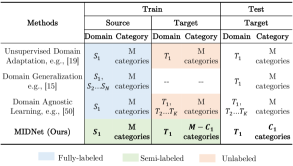

Previous domain adaptation approaches consider three domain adaptation settings regarding to the number of domains, including one-to-one domain adaptation, multi-source domain adaptation and multi-target domain adaptation. One-to-one domain adaptation considers a single source domain and a single target domain. Unsupervised domain adaption [19, 32, 43] is a typical one-to-one domain adaptation, which requires plenty of labeled samples from the source domain during training and categories in both domains are the same. Multi-source domain adaptation learns universal knowledge from multiple source domains to a single target domain [49]. Domain generalization [15, 35] is a special case of multi-source domain adaptation, which learns knowledge for an unseen target domain from many labeled samples of multiple source domains. In domain generalization, each category in the target domain has been seen in at least one source domain. Multi-target domain adaptation learns knowledge from a single source domain to multiple target domains. Domain agnostic learning [50] is a multi-target domain adaptation method, which also requires plenty of labeled samples from the source domain. In domain agnostic learning, all categories in target domains have been seen in the source domain.

In this paper, we consider a one-to-one domain adaptation setting. In contrast to other works of one-to-one domain adaptation, in our work, the categories in the target domain are a subset of the categories in the source domain. Our ultimate goal is to learn categorical-discriminative knowledge from available categories in both domains to separate unseen categories in the target domain. Fig. 3 compares the different task settings between our work and other domain adaptation works.